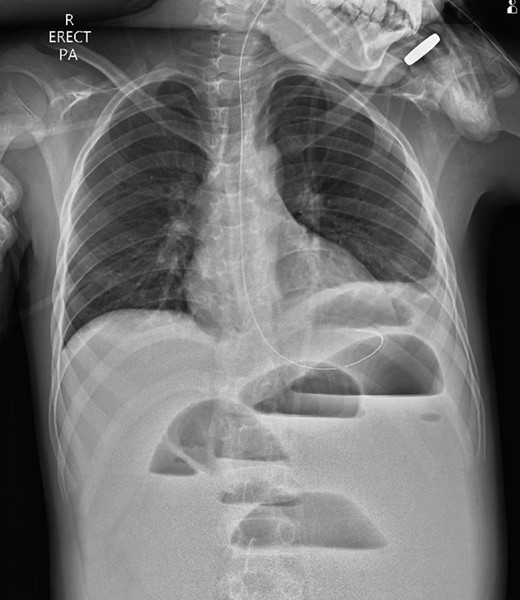

A 10-year-old boy presented unwell with generalized peritonitis after 3 days of abdominal pain, nausea and anorexia. He had a low-grade fever but all other vitals were within normal limits. Blood tests showed a raised white cell count of 16 × 109 with neutrophilia and raised C-Reactive Protein of 127 mg/l. Laparoscopy revealed generalized purulent peritonitis secondary to perforated appendicitis. Appendicectomy was performed and the appendiceal stump was secured. Lavage of the abdomen was performed with a minimum of four litres of warmed normal saline. Fluid was suctioned, an abdominal drain was placed and the pneumoperitoneum was deflated. By the second postoperative day, he developed an ileus with persistent vomiting (Fig. 1). This was managed conservatively with nasogastric intubation, bowel rest, electrolyte replacement and fluid therapy. It became clear by the fifth postoperative day that the patient had intestinal obstruction. On examination, he had a distended abdomen, with intractable nausea and vomiting. Blood tests revealed a normal white cell count and potassium remained at 3.3 despite supplemental intravenous replacement. Abdominal X-ray revealed a small bowel obstruction and he was taken back to theatre for an emergency laparotomy (Figs 2 and 3). A small bowel volvulus was discovered, with no evidence of intestinal malrotation. The volvulus involved a segment of distal jejunum to proximal ileum causing complete small bowel obstruction.

Erect chest radiograph on postoperative day 2 suggestive of small bowel ileus.

Erect chest radiograph on day 5 more consistent with small bowel obstruction.